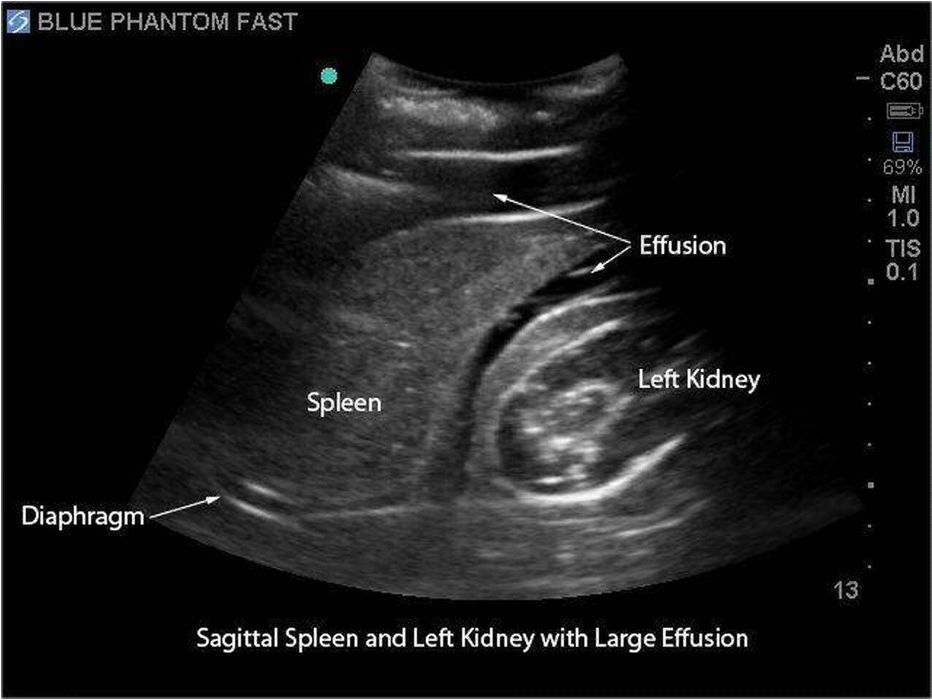

What does this refer to

Diagnostics for abdominal and GU trauma

FAST exam